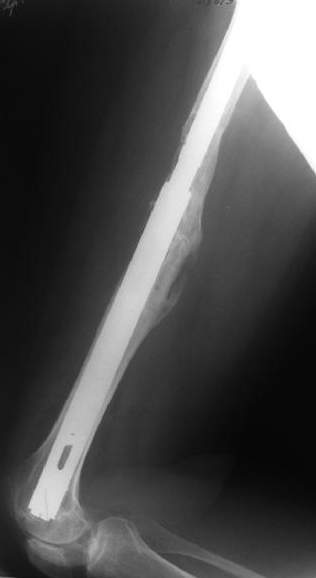

I heard from many european colleagues about anecdotal use of old hollow Kuntscher nails for that purpose. Prof. R.Schnettler (Germany) recently told about 57 cases. I have only 2 such cases done last year, both on cementless stem. This approach is very attractive by that we achieve the same goal - "new long stem" but much less invasive.

Female, rheumatoid, THA in 2003, car accident in 2006, failed plating. Nailing in Oct 2007. The nail is solid with hollow proximal part where the stem is docked. Last images are in 1 year after

nailing.

I have refreshed respect for the mighty femur and it’s incredible/remarkable ability to unite, regardless of what we do to it.

The femur responded by failure to Mennen plating (DePuy Bridge plate). So i would add that the ability to unite is realized in mechanically and biologically sound conditions.